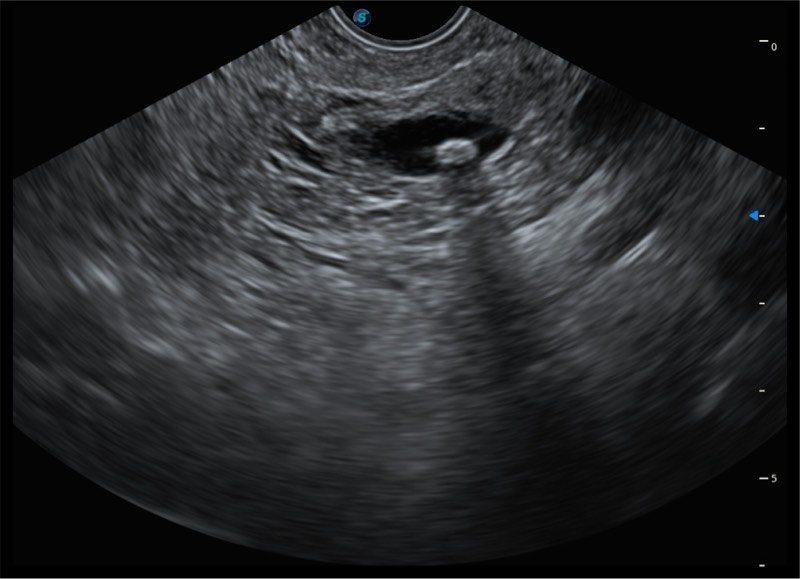

搭载百万级CMOS成像技术

及自主研发凸阵换能器,

可呈现优质的内镜和超声画面

基于二十年的超声技术积累,开立提供了最新一代的独立超声主机,在提供高质量图像的同时满足多学科使用。具备常见多普勒技术并提供弹性成像、声学造影等高端影像技术。新一代传感器具有更强的抗干扰能力并减少图像伪影。

150°超声扫描角度

4-12MHZ宽频输出